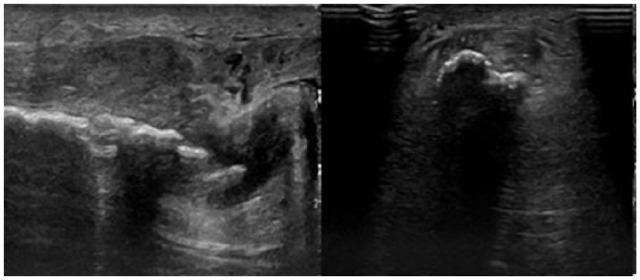

We report the case of a 66-year-old male patient with massive ossification of the distal portion of the Achilles tendon, as a late consequence of a surgical release for club foot conducted in his childhood. The singularity of the case report derives from its clinical features: the bone mass was of abnormal dimensions, almost substituting the entire tendon; the condition had always been asymptomatic, without deficits in range of motion, in absence of either pain or biomechanical defects with age. In fact, the condition was diagnosed just recently as a consequence of a tear. Despite an ultrasound diagnosis after the injury, only during the surgical treatment, a proper evaluation of the entity of the pathology was possible. Although the ossification of Achilles tendon is a rare clinical condition with a complex multifactorial etiology, in our case report, some of the elements in the patient's medical history could be useful for the pathogenesis and early diagnosis of the disease. The aim of this case report is to emphasize the importance both of a correct evaluation of clinical history and of an accurate diagnosis, in order to conduct a proper management of this pathology.